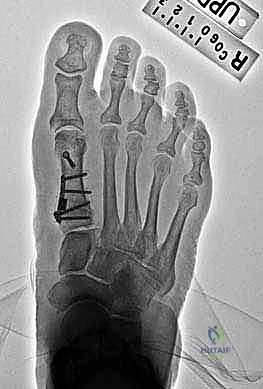

The plate has been set into position by insertion of the first screw.

3. Second Screw Placement: The next screw is placed in one of the proximal holes. We prefer to place both of these initial screws obliquely across the apex of the osteotomy. This provides excellent compression and stability across the osteotomy site.

4. Additional Stability: If there is any concern about stability, an additional oblique screw can be placed outside the plate, crossing the osteotomy to enhance the construct. To gain further support to the lateral cortex, one of the proximal screws may be placed not only through the plate but also across the osteotomy to capture the distal lateral cortex.

5. Final Screw Placement: The remaining screws are then placed distally and proximally to complete the fixation. Ensure all screws are appropriately seated and provide rigid fixation.

6. Final Fluoroscopic Check: With the plate securely fixed, we'll perform a final fluoroscopic check with the foot flat on the table. We'll verify a congruent MTP joint and ensure the IMA and DMAA are within acceptable limits. If the joint was congruent preoperatively with an increased DMAA, we confirm that the DMAA has been adequately addressed.

Six week postoperative weight-bearing AP radiograph shows good alignment post-PMOW first metatarsal and distal biplanar chevron bunionectomy.